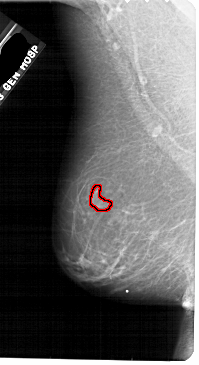

A_1884_1.RIGHT_CC

RIGHT_CC LINES 5416 PIXELS_PER_LINE 2746 BITS_PER_PIXEL 12 RESOLUTION 43.5 NON_OVERLAY

FILE: A_1884_1.LEFT_CC.OVERLAY

TOTAL_ABNORMALITIES 1

ABNORMALITY 1

LESION_TYPE MASS SHAPE LOBULATED MARGINS OBSCURED

ASSESSMENT 4

SUBTLETY 3

PATHOLOGY BENIGN

TOTAL_OUTLINES 1

BOUNDARY